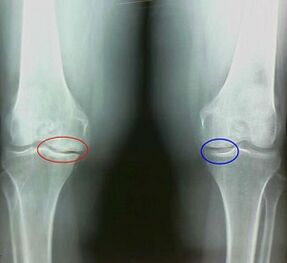

For example, what is the difference between arthritis and knee joint arthrosis?With arthritis, synovial synovial shells occur.This causes an increase in temperature in the joints.

Joint sturdy, persistent pain syndrome develops, increasing during movement.With arthrosis, pain occurs only after physical activity, you can hear a feature crisis or click on the joints, gradually -the joints are defective and loss of mobility.